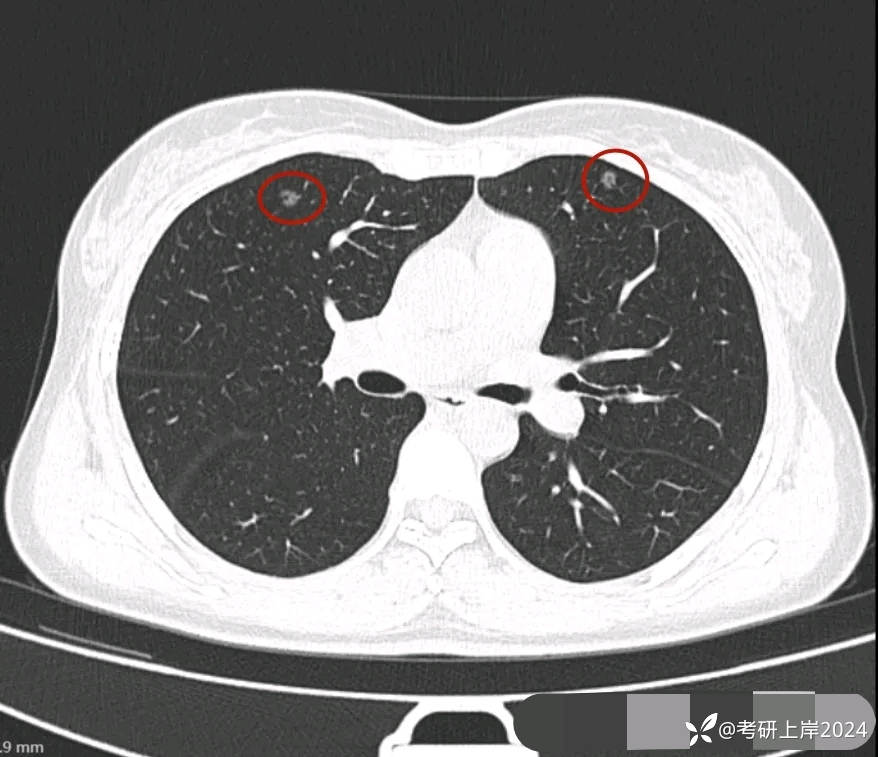

患者最近的检查有AI辅助诊断意见,找出的病灶分别如下:

病灶24:右下叶叶裂处结节,实性,边缘光滑,没有收缩力,密度过高,考虑肺内淋巴结或碳沫沉积可能性大。2023年12月最明显的结节形态:

与2024年3月份复查时的对比,几乎没有变化。我的回复:两肺多达20几处结节,除了最后一处实性的考虑良性的,其他的都是磨玻璃密度,整体轮廓较清的,这在3月份的AI诊断上都有截图,其中最主要的几处就是我另外再截图了发来的这几处。它们也仍算是磨玻璃密度,病理大概会是原位癌可能性大,个把最坏可能是微浸润性腺癌,其实说不上明显实性成分,只是右上叶的那三处,最靠纵隔的那枚有血管穿过,显得像是混合密度,但肿瘤的成分仍是磨玻璃的。鉴于多发,又无法都通过手术全部切除,我的想法仍是再观察随访为主,待主病灶进展到有风险了再来考虑干预处理主病灶,并到时候兼顾同侧的其他结节是否顺带解决一部分。目前先随访,意见供参考!感悟:今天为什么要分享其实挺常见的这种多发磨玻璃病例?我想主要是由于结友问诊了这么多医生,仍在继续问,说明她虽然这些结节目前风险不大,但对她的心理造成了很大的压力,这也是结友最常见的心理状态。我觉得心理的崩溃或不断钻牛角尖的思考或许在短期内导致的害处更甚于结节本身!她问了这么多医生,肯定大部分都认为能随访,目前也没有风险大到定得赶紧处理的病灶,但她仍在不停的问诊,总想得到更让其踏实的答案。但哪位医生能说这些不是恶性范围的呢?谁能告诉她这是正常的呢?那不可能呀!已对查出多发结节,致病因素不明、预防措施没有、切又切不光、用药也不用!你说除了正确认识它、理性面对它,你能如何?在问诊中,总是有结友问到底有没有增长1毫米?CT值有没有增加?血管有没有进入?空泡有没有?实性成分有没有以及占多少?这些作为患者自己定要去纠结有何益?能说明什么问题呢?总体上,如果像今天这位结友医院提供AI辅助诊断意见,那是大小、体积、CT值、风险程度都会列的清清楚楚。但实际上在临床工作中,医生并不必这样按数值去判断风险或决定是否手术,如果这样还需要医生干嘛,AI全部会给出意见,AI说该开刀的转给胸外科、AI说可随访的回家下次来复查、AI说有风险的去消融等等。事实上我一直认为,我们看肺多发结节,关键就抓住:1、最主要的病灶风险如何:如果主病灶仍是危险性不高能随访,那么既无必要去数一共是10处还是15处,抑或20处,都没有意义,因为反正是按时复查就行;2、不同时期影像的对比,过于细微的差别,当其不足以改变临床决策的时候,就失去了深究的意义:纯磨只需随访的,你是5毫米也好,7毫米也罢,有何相干?反正仍不需干预处理。实性结节怕它危险,但若2毫米、3毫米,连影像特征都看不明白,更不可能为了这类结节去切下来化验,那么总在担心到底良性还是恶性,会不会是小细胞癌有何用?所以我在临床工作中,基本上不在意具体大小,也不去测CT值,关注一是实性成分有没有;二是血管有没有进入以及异常增粗;三是对比最早的与最近的有没有明显变化。放平心态、理性面对,该随访时按时随访,该干预时下决心干预!